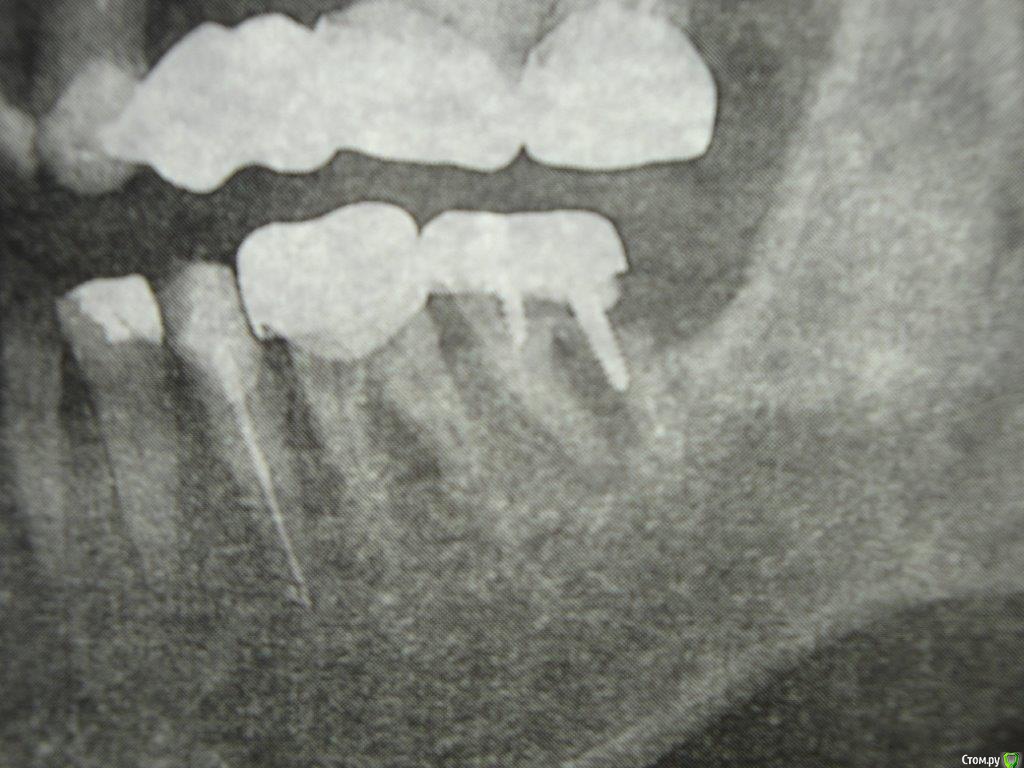

Коша Опубликовано 26 апреля, 2016 Поделиться Опубликовано 26 апреля, 2016 Здравствуйте!Подскажите пожалуйста!можно ли восстановить 7снизу слева зуб. пару врачей мне сказали, что нужно удалять, но вера в современную стоматологию, еще теплит надежду, что возможно еще можно над ним поработать, и пока оставить его!Зуб не болит, я им жую, но стала образовываться щель между телом зуба и краем коронки.Есть несколько снимков (отрывки с панорамных снимков)- прилагаю их. Ссылка на комментарий